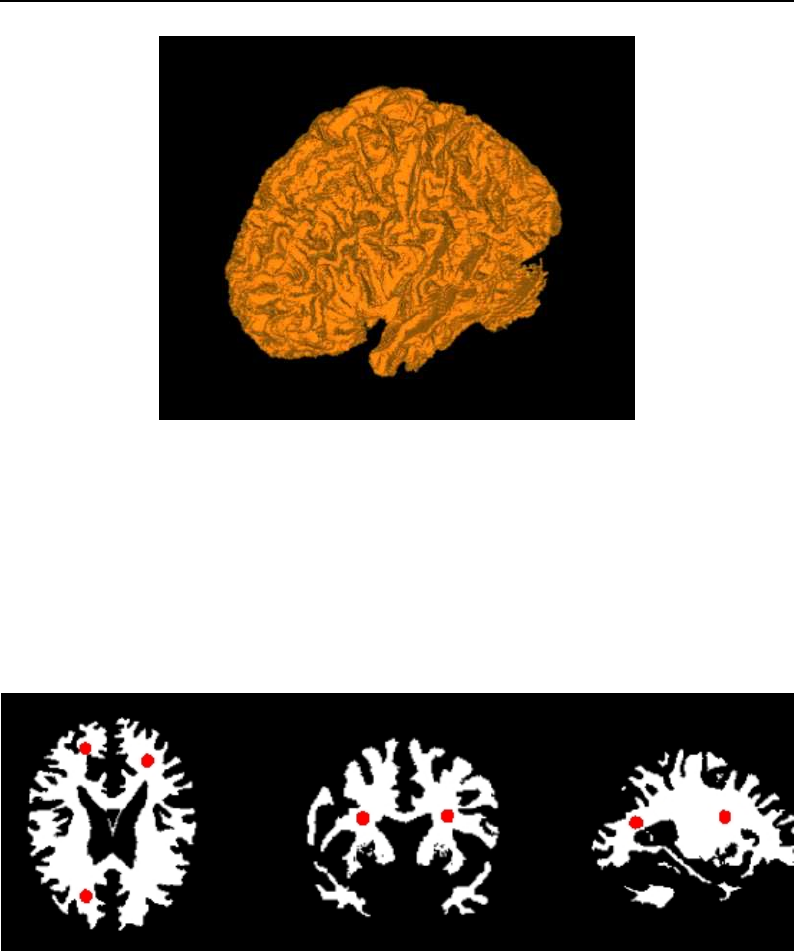

The National Library of Medicine Insight Segmentation and Registration Toolkit, shortened as the

Insight Toolkit (ITK), is an open-source software toolkit for performing registration and segmenta-

tion. Segmentation is the process of identifying and classifying data found in a digitally sampled

representation. Typically the sampled representation is an image acquired from such medical instru-

mentation as CT or MRI scanners. Registration is the task of aligning or developing correspondences

between data. For example, in the medical environment, a CT scan may be aligned with a MRI scan

in order to combine the information contained in both.